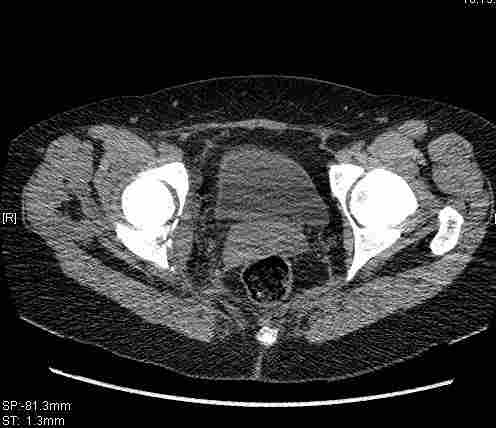

Женщина,58 лет, после ДТП 6 суток. Первично повреждение расценено как переломы ветвей лонной кости. После подтверждения повреждения вертлужной впадины,как чаще всего случается, вопрос встал о тактике. БОльшинство за консерватиное лечение.К сожалению кт у нас "во время" сломался. Прилагаю стандартные снимки вертлужки. У меня следующие вопросы к коллегам:1. Правильно ли рассценивать это повреждение как Т-образный перелом вертлужнй впадины?2. Можно ли добиться анатомической репозиции поверхности вертлужной впадины скелетным вытяжением в данном случае, если нет, что будет этому препятствовать?3. Если смещение останется таким как сейчас, через какое время появится необходимость эндопротезирования (по вашему опыту)?Спасибо.

Удалось сегодня вывести пациентку в соседнюю больницу, где есть кт. Срезы сделаны только горизонтальные.

|

имеется передний подвывих, головка нагружаемой зоной будет "тереться" о край фрагмента, связанного с осевым скелетом.

вероятность быстрого прогрессирования коксартроза велика, хотя вряд ли кто-то укажет конкретные сроки. 1 год - 1,5 ?